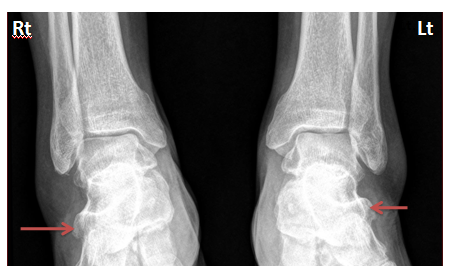

Radiography of both ankles

Anteroposterior view of the right and left ankles showed bilateral hypertrophic peroneal tubercles on the lateral side of calcaneal bones (Figure 2).

Figure 2 AP view of both right (Rt) and left (Lt) ankles revealed enlarged bilateral peroneal tubercles on the lateral side of calcaneal bones (red arrows).